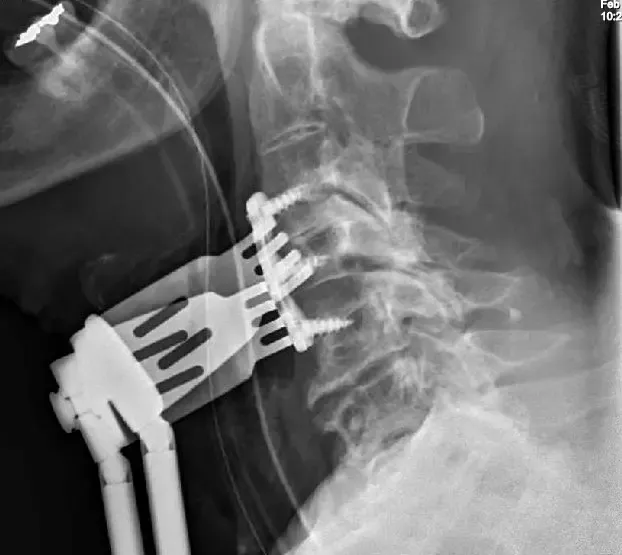

Radiografías Vista lateral de la columna cervical que muestra enfermedad degenerativa avanzada de la columna cervical

Se realizó discectomía cervical anterior y fusión para aliviar la presión de la médula espinal, con limpieza a disco y fusión utilizando injerto óseo y placas y tornillos desde la parte frontal.